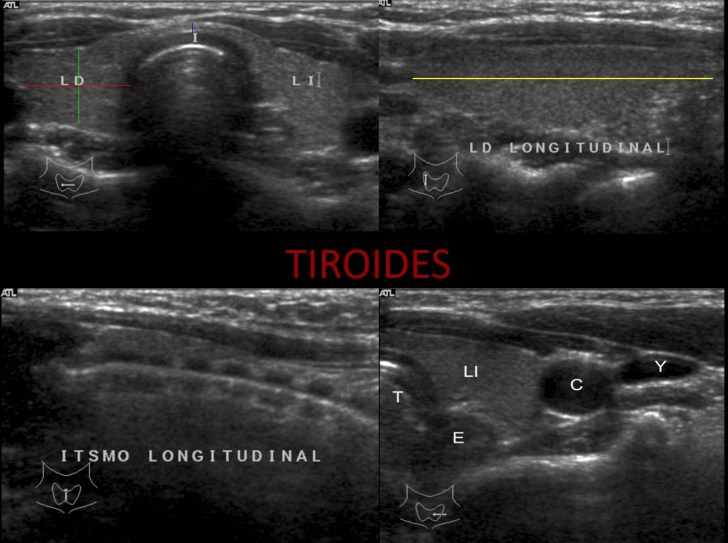

Sabemos que cuando vemos un paciente con su tiroides normal, vemos esto:

cuando hacemos un tiroidectomizado, vemos esto:

Quiero que veas las dos imágenes y compares.

Lo más importante, saber cómo es la «normalidad» de una región tiroidectomizada, te la dejo en las dos siguientes imágenes, veremos una zona hiperecogénica correspondiente a la grasa que ocupa el espacio que ya no ocupa el tiroides. Cuando el paciente es diagnosticado de ca de tiroides suele realizarse tiroidectomía total.